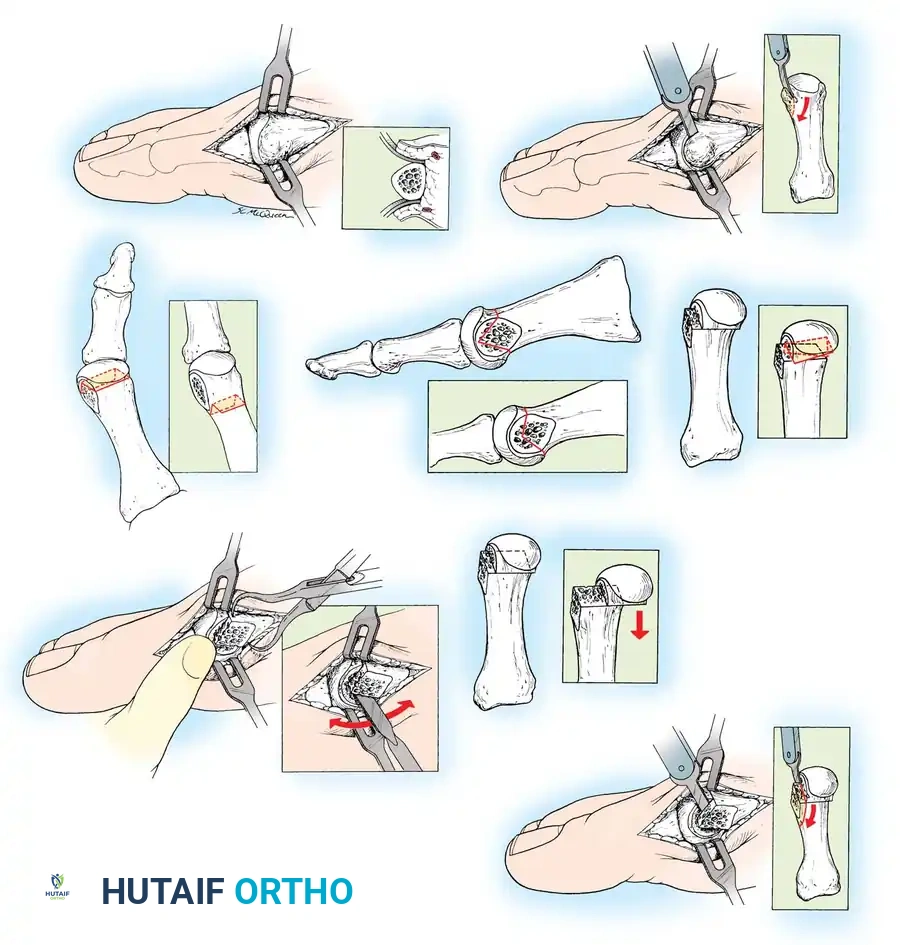

Keller Resection Arthroplasty The Keller procedure combines resection hemiarthroplasty of the fi rst metatarsophalangeal joint with removal of the medial eminence of the fi rst metatarsal (Fig. 78-28). Although removing the base of the proximal phalanx decompresses the joint and mobilizes the hallux, allowing marked correction of valgus, the varus of the fi rst metatarsal is not corrected, and maintaining correction of the valgus of the hallux is diffi cult. Other complications of the Keller procedure have been emphasized in the literature to such an extent (with neither the incidence nor the severity of such complications clearly documented) that the indications for this procedure have been limited severely. In our experience, however, complications are uncommon if patients are selected carefully. Modifi cations in the original technique also have allowed expansion of the indications for the Keller bunionectomy. Candidates for the Keller procedure are patients older than 50 years with moderate-to-severe hallux valgus (30 to 45 degrees); intermetatarsal angles of 13 degrees or less, indicating mild-to-moderate metatarsus primus varus; and pain over the medial eminence with any shoe worn, so the variety of shoes the patient can wear is severely limited. An incongruous fi rst metatarsophalangeal joint caused by

Fig. 78-26 Modifi ed McBride bunionectomy (DuVries; Mann). A, Medial capsule of second metatarsophalangeal joint is sutured to lateral capsule of fi rst metatarsophalangeal joint with interposition of released adductor hallucis. B, Medial capsular resection. C, Confi guration after capsular resection. D, After capsular imbrication, hallux should rest in neutral position or not exceed 5 degrees of varus. E, Postoperative dressing technique (Mann). ( E after Beverly Kessler; courtesy of LTI Medica and The Upjohn Company.) lateral subluxation of the phalanx on the metatarsal head, severe lateral displacement of the sesamoids, and any evidence of degenerative cartilage changes in the joint all are radiographic indications for the Keller procedure. Two modifi cations in technique can expand these indications, however, to include patients with more severe deformities (Fig. 78-29) (but not to include younger patients): fi bular sesamoidectomy and lateral displacement of the fi rst metatarsal. Using these modifi cations, Donley et al. obtained an average 18-degree correction of the metatarsophalangeal angle and an average 6-degree correction of the intermetatarsal angle in 38 patients (50 feet);

95% of patients were satisfi ed with their results. Patients with 50 degrees or more of valgus of the hallux (18 to 20 degrees of varus of the fi rst metatarsal), complete lateral dislocation of the sesamoids, marked degenerative changes, and severe pronation of the hallux may benefi t functionally and cosmetically from alterations of the standard technique.

🔪 Surgical Technique 78-2

• If pedal pulses are good, use an Esmarch wrap tourniquet.

• Use 1% lidocaine (Xylocaine) and 0.5% bupivacaine (Marcaine) in equal portions within standard dose limits for the forefoot block.

• Make a straight midline medial incision 1 cm proximal to the interphalangeal joint of the hallux, and extend it proximally to the junction of the distal and middle thirds of the fi rst metatarsal. This lengthy incision is made to avoid excessive traction tension on the skin.

• By blunt dissection, locate the most medial branch of the superfi cial peroneal nerve at the proximal-dorsal edge of the medial eminence, and retract it for protection.

• Carry the dissection to the fi rst metatarsal in the midline medially, beginning in the proximal limit of the wound and extending distally across the midline of the medial eminence and along the proximal phalanx to the distal extent of the wound.

• Raise the deep fl ap of tissue by sharp dissection dorsally, beginning at the junction of the medial eminence and shaft of the fi rst metatarsal.

• Raise the periosteum and capsule dorsally up to one third to one half the width of the metatarsal.

• At the joint, continue the capsular elevation along the extensor hallucis brevis insertion until the proximal third of the proximal phalanx is exposed as far laterally as possible under direct vision. To make exposure easier, have an assistant pronate the hallux as the dissection proceeds laterally. Subperiosteal dissection should expose only the portion of the proximal phalanx that is to be removed.

• Plantarly dissect just enough to expose the plantar aspect of the medial eminence proximally, the tibial sesamoid in the center of the wound, and the plantar-medial corner of the proximal phalanx.

• Supinate the proximal phalanx to expose the plantar corner and proximal third of the shaft for the sharp dissection. The proximal phalanx is round on three sides, but its plantar surface is fl at and even concave in the midline where the fl exor hallucis longus tendon passes. This change in contour must be taken into account when dissecting to avoid injury of the fl exor hallucis longus tendon.

• By blunt dissection, identify the fl exor hallucis longus tendon, and retract it plantarward with a small right-angle retractor to protect it throughout the dissection of the proximal phalanx.

• Resect the medial eminence at the sagittal groove, beginning dorsally at its distal edge and directing a 9-mm oscillating blade

A B

C

D

Fig. 78-29 Severe hallux valgus with bursa formation in 70-year-old woman. A and B, Anteroposterior and lateral clinical photographs of patient’s right foot. C, Correction of deformity by modifi ed Keller procedure. D, Preoperative and postoperative weight bearing radiographs of same patient.

🔪 Surgical Technique 78-2

(or osteotome) plantarward and slightly medially (5 to 10 degrees).

• Remove the base of the proximal phalanx at the metaphysealdiaphyseal junction, which usually constitutes the proximal third of the phalanx (Fig. 78-30A and B). To prevent damage to the fl exor hallucis longus and the neurovascular bundles, place a retractor over the bone dorsally and plantarward, and rotate the phalanx into view. Also, do not allow the saw blade to exit bone more than 1 to 2 mm.

• When the osteotomy has been completed, grasp the basilar fragment with a small Kocher clamp or towel clip, and rotate the fragment while applying medial pull to excise it. Lift it away from its lateral attachments, which are primarily the lateral collateral ligaments and the adductor muscle tendinous insertion (Fig. 78-30C).

• With the ankle at 90 degrees, bring the hallux into a corrected position, while manually pushing the fi rst metatarsal as far laterally as possible. Evaluate the alignment, keeping the metatarsal and hallux straight.

The following modifi cations of the Keller technique can expand the indications for use with more severe deformities.

REMOVAL OF THE FIBULAR SESAMOID

• When the medial eminence and phalangeal base have been excised, remove the fi bular sesamoid.

• Place a sturdy two-toothed retractor beneath the metatarsal head, and have an assistant lift it dorsally.

• Using a Freer elevator or a small osteotome for its strength, mobilize the fi bular sesamoid (Fig. 78-31A to C). This may be diffi cult in elderly patients with signifi cant deformity and adherence of the sesamoid to the metatarsal head. Lift the metatarsal dorsally for exposure (Fig. 78-31D and E).

• When the sesamoid is mobile, identify the fl exor hallucis longus tendon by placing traction on the hallux and fl exing and extending the interphalangeal joint of the hallux. The tendon is visible just distal to and in alignment with the sesamoids, which straddle it.

• Identify and expose the lateral neurovascular bundle just lateral to the tendon by blunt dissection.

• Pull the plantar medial capsule medially. This requires a fi rm grasp on the capsule. The medial traction brings the intersesamoid “ligament” into better view.

• Incise the intersesamoid ligament longitudinally with a No. 67 Beaver or No. 15 Bard-Parker blade. If tenotomy scissors are used, place one arm of the scissors under the ligament (this arm rests on the dorsal side of the fl exor hallucis longus) and the other arm dorsal to the ligament.

• When the intersesamoid ligament is incised, grasp the sesamoid fi rmly with forceps or a small Kocher clamp, fl ex the toe at the interphalangeal and metatarsophalangeal joints to relax the fl exor hallucis longus tendon, and pull the fi bular sesamoid distally and medially.

• With release of the intersesamoid ligament, the medial surface of the fi bular sesamoid is free from soft tissue. Distally, the sesamoid is free because of resection of the base of the proximal phalanx. This leaves two sides of the sesamoid, distal and medial, free of soft tissue.

• While pulling the sesamoid distally and medially, use a small blade to incise along the lateral margin of the sesamoid under direct vision. Keep pulling the head of the metatarsal dorsally and holding the hallux distracted and in fl exion. This greatly aids in identifi cation of the margins of the fi bular sesamoid, particularly laterally and proximally.

• The most diffi cult part of the sesamoidectomy and that which should be done last is release of the proximal lateral corner of the sesamoid where the fl exor hallucis brevis lateral head inserts. While incising the lateral capsular attachments to the sesamoid, do not bury the blade of the knife because the neurovascular bundle to the lateral side of the hallux is just lateral to the capsule.

• Now all attachments to the fi bular sesamoid have been removed except the lateral head of the fl exor hallucis brevis, which inserts on the proximal lateral margin of the sesamoid. This is a diffi cult section to remove; however, this section can be released under direct vision by pulling the sesamoid distally and medially and lifting the metatarsal head dorsally with a strong two-toothed retractor.

• When the sesamoid has been removed, insert two 0.062-inch Kirschner wires retrograde from the tip of the toe 2 to 3 mm plantar to the nail bed, leaving about 5 to 7 mm of the pins exposed at the base of the phalangeal remnant to help align the phalanx on the metatarsal before antegrade passage of the pins into the metatarsal (Fig. 78-31F).

LATERAL DISPLACEMENT OF THE FIRST METATARSAL

• Push the metatarsal laterally several times. Occasionally, this does not move the metatarsal, but some lateral mobility usually is present.

Fig. 78-31 Excision of fi bular sesamoid in modifi ed Keller procedure. With base of proximal phalanx removed and medial eminence excision, exposure of fi bular sesamoid is not as diffi cult from medial incision. A, Operative photograph showing elevation of fi rst metatarsal with strong two-tooth retractor and use of small osteotome to mobilize fi bular sesamoid and lateral capsuloligamentous (frequently contracted) structures. Osteotome is between metatarsal head and lateral sesamoid. When mobilization of fi bular sesamoid is complete, entire sesamoid is visible for excision. Note chondromalacia of tibial sesamoid articular surface medial to osteotome. B, Fibular sesamoid has been excised, and lateral capsular structures and conjoined tendon (in forceps) have been released. Neurovascular bundle to lateral side of hallux is adjacent to these structures. C, Diagrammatic representation of modifi ed Keller procedure. By excising fi bular sesamoid, valgus moment of conjoined tendon of fl exor hallucis brevis and adductor hallucis no longer pulls fl exor hallucis longus tendon laterally (carrying hallux with it) through capsulosesamoid plantar plate and pulley system. D, Metatarsal head must be lifted dorsally to excise fi bular sesamoid under direct vision. E, Note exposure of fi bular sesamoid after mobilization of metatarsal head. Continued